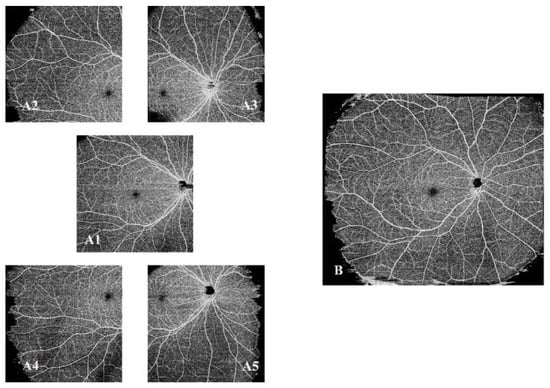

2.4. SS-OCTA Image Quantification of DWOP Lesion Areas